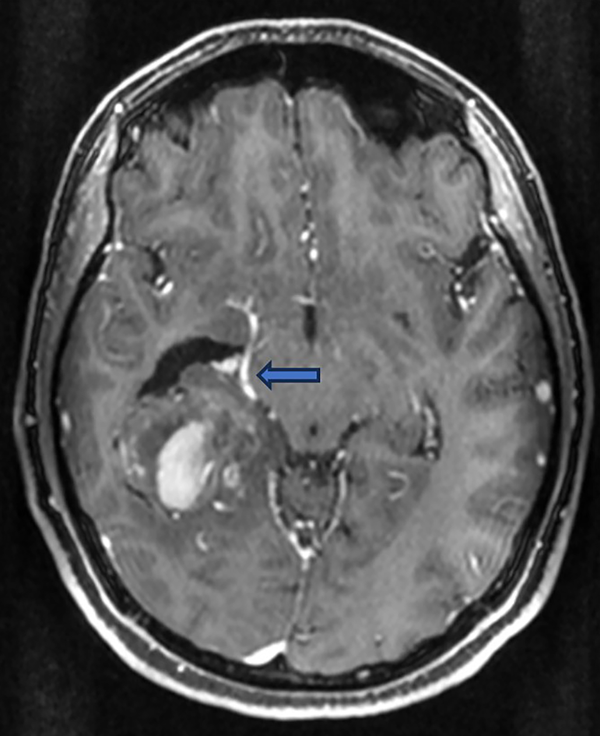

La paciente fue operada mediante un abordaje supraauricular derecho transtemporal en el que se logró una resección macroscópica satisfactoria (>90%). Desde el punto de vista intraoperatorio, se resecó toda la lesión de características visualmente sospechosas, ya que por momentos no tenía un plano anatómico diferenciable respecto al tejido sano, y se dejó un remanente hacia medial para respetar y no dañar el pasaje de la arteria cerebral posterior o alguna de sus ramas (Figura 2). Se decidió dejar un drenaje ventricular externo (DVE) que fue retirado a las 48 horas postoperatorias.

Figura 2. RM: corte axial en T1 con gadolinio, donde se observa una posible relación de la masa tumoral con la arteria cerebral posterior derecha (o alguna de sus ramas) hacia el borde medial de la lesión (flecha azul).